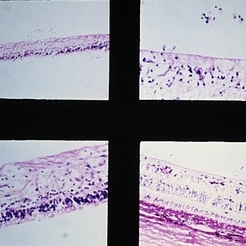

Lattice degeneration of retina with retinal holes. Microscopic appearance at three levels (upper, right, and lower) shows discontinuity of the internal limiting membrane, an overlying pocket of fluid vitreous, atrophy of inner retinal layers, hole formation, and vitreoretinal adhesion (arrows) at margin of lesion. (E.P. No. 30544)

Condition/keywords: atrophy, retinal degeneration, retinal hole, vitreoretinal adhesion